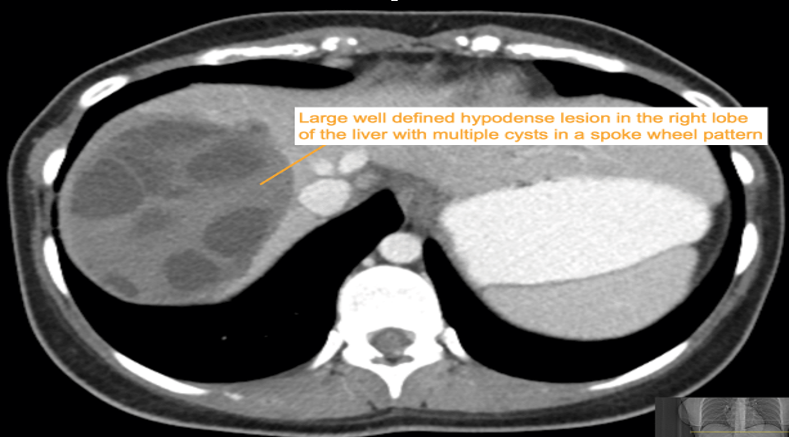

CASE 3 – A 23-year-old woman presents with 3 weeks of right upper quadrant (RUQ) pain associated with early satiety. The patient has no significant past medical history. She was born in Iraq and migrated to Australia from Syria 2 years prior to presentation. Preliminary blood results demonstrate moderate liver function test (LFT) derangement.

EXPLANATION -The case demonstrates classical appearance of a hepatic hydatid cyst. There is a well-defined rounded lesion in right lobe of liver with multiple small daughter cysts within. The fluid in the cysts can be of variable density depending on the proteinaceous contents (more protein = more dense). The thick internal septae can give a “spoke wheel” appearance as in this case. Curvilinear calcifications represents the inactive stage of the disease.

Hydatid diseases a parasitic zoonosis, caused by the larval stages of the Echinococcus granulosus .

- E. granulosusis found worldwide, however the highest rates of infection are seen in the Mediterranean and Middle Eastern regions, North Africa and South America.

- Hydatid cyst can occur anywhere in the body, the most commonly affected organ is the liver (76% of cases), followed by lung (15%) and spleen (5%).

- Classically there is a large ‘parent cyst’ which contains numerus peripheral ‘daughter cysts’.

- Humans are infected by eating the eggs of the tapeworm E. granulosus, by either eating contaminated food or through contact with dogs.

- The ingested embryos invade the intestinal mucosal wall, enter the portal circulation and develop cysts in the liver.

- Treatment options ; Surgical excision, PAIR (Puncture, Aspiration, Injection of protoscolicidal agent and Re-aspiration), Anti-helminthic agent (e.g. albendazole, mebendazole), Observation only – for inactive and silent cysts